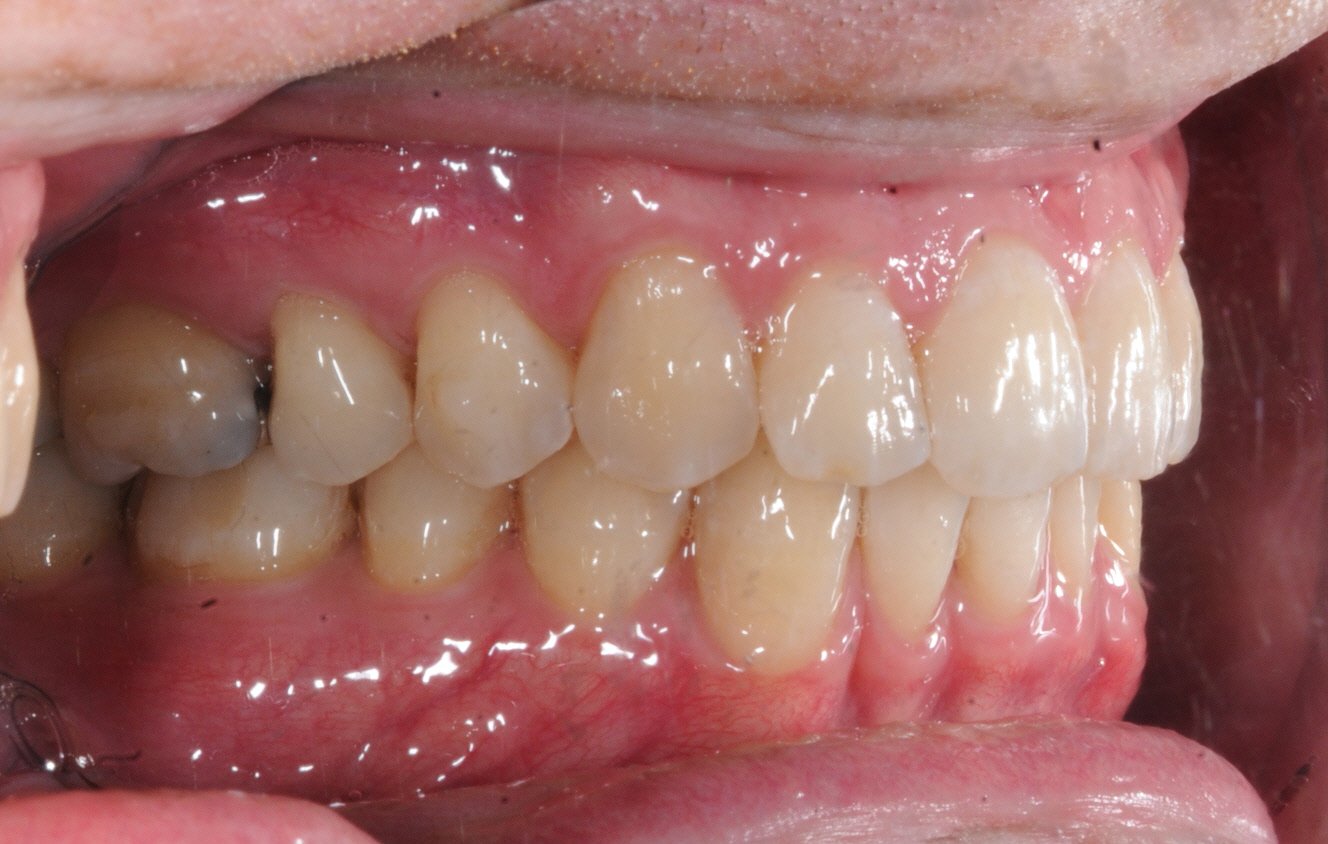

Walker’s Smile Journey: A Stunning Finish in Just 1 Year!

These results are nothing short of amazing! Take a look at how well aligned his teeth are and how healthy the tissue on the bottom looks.

Here’s the big reveal: it took just 1 year to complete the treatment for his lower teeth with Inbrace! In fact, the Inbrace system finished aligning the lower arch faster than the upper aligners. A testament to the predictability of the Inbrace system.

Even after these final photos were taken, we continued using clear aligners on the top teeth for some fine-tuning, ensuring every detail of Walker’s smile is perfect.

From crowded and misaligned teeth to a confident, healthy smile, Walker’s journey shows what’s possible with a carefully crafted treatment plan with Dr. Andrew!